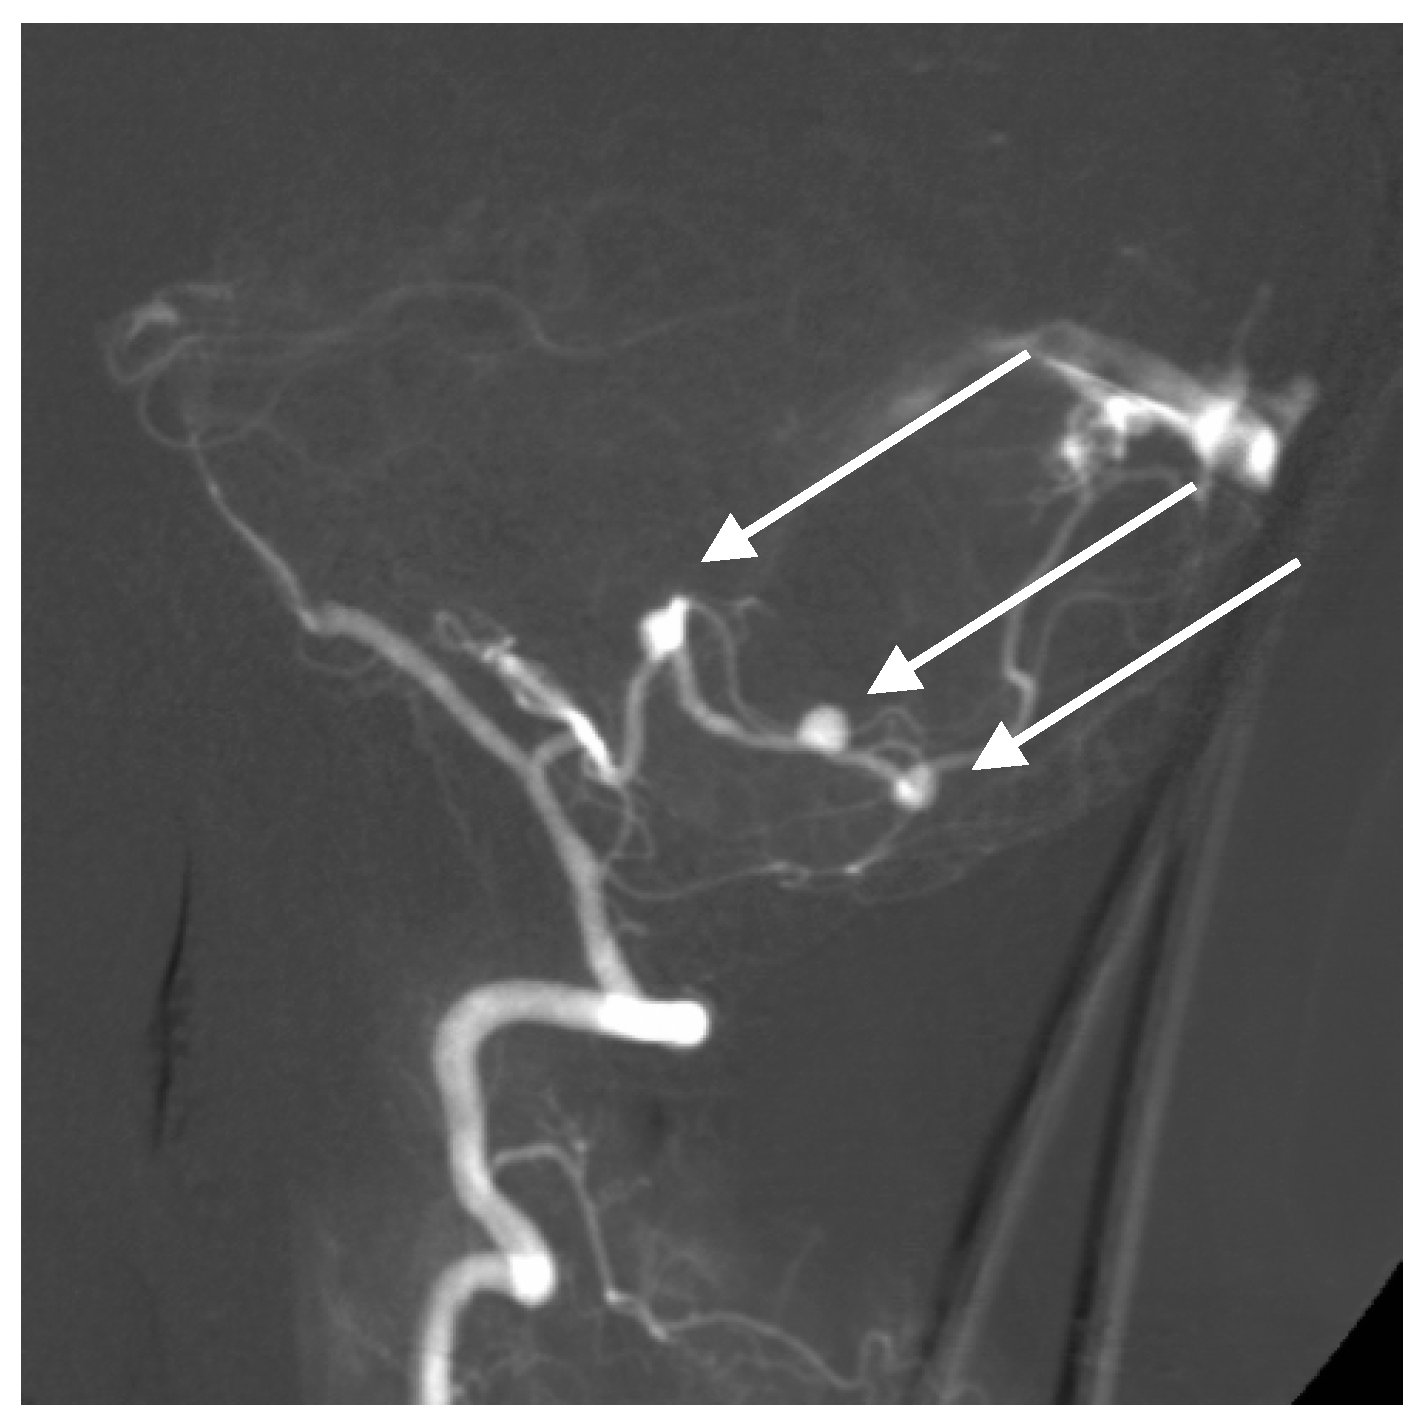

A 50-year-old man presented with a headache. Magnetic resonance imaging (MR) and angiography showed cerebellar AVM and two aneurysms on the right side of the PICA (Figure 6 and Figure 7). The patient underwent an operation, and AVM was successfully resected with both aneurysms clipped. The control angiogram showed good result of the treatment (Figure 8), the postoperative course was without complication, and the patient was discharged.

Figure 7. Lateral angiogram showing cerebellar AVM and two PICA aneurysms.

Figure 8. Postoperative control with radical AVM resection and successful clipping of PICA aneurysm.